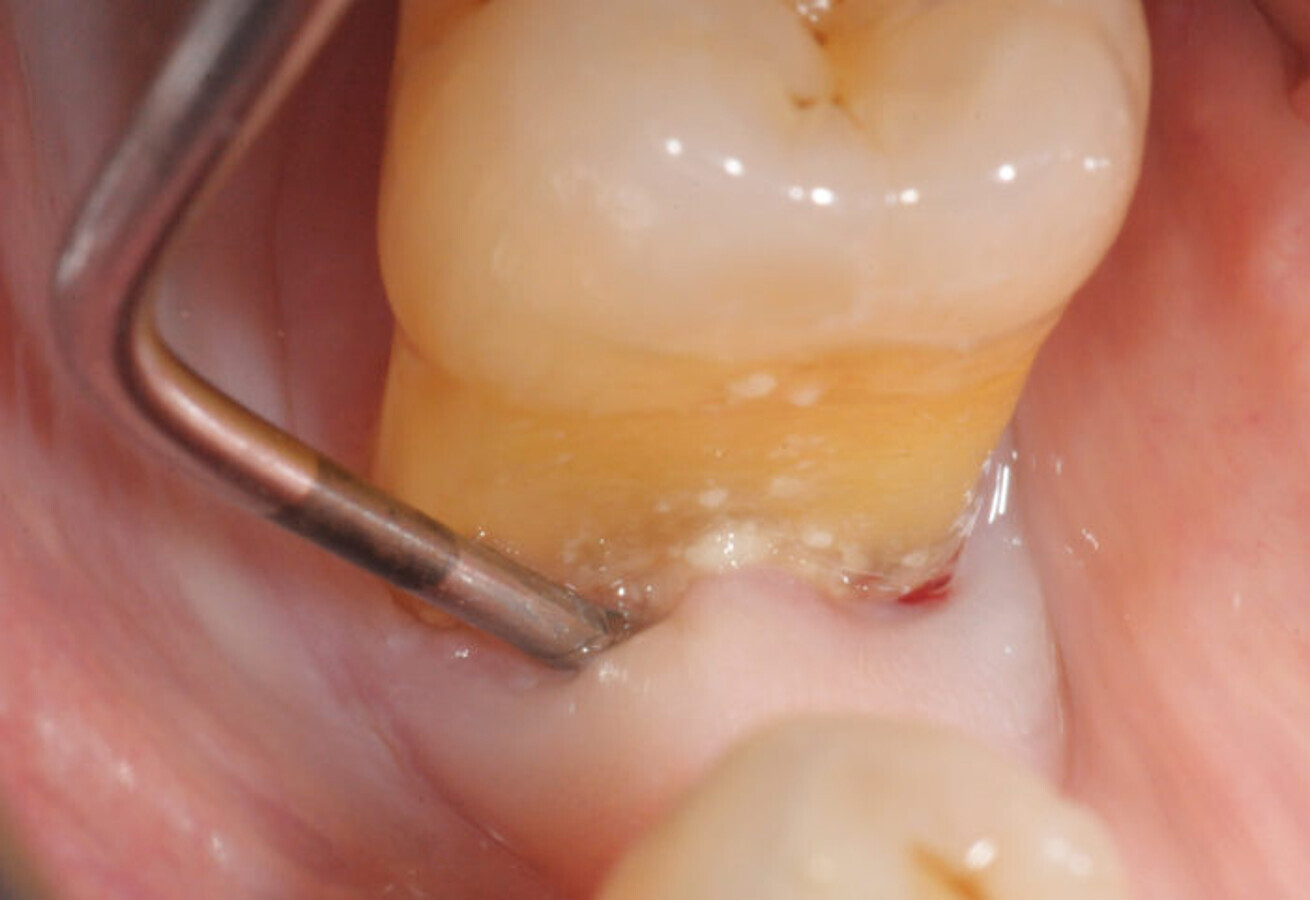

Fig. 2

Periodontal cleaning

It is preferable to use subgingival tips (Fig. 2), normally indicated for periodontal sites over 5 mm deep. These allow us to limit excesses of the jet by directing it entirely into the periodontal pocket.